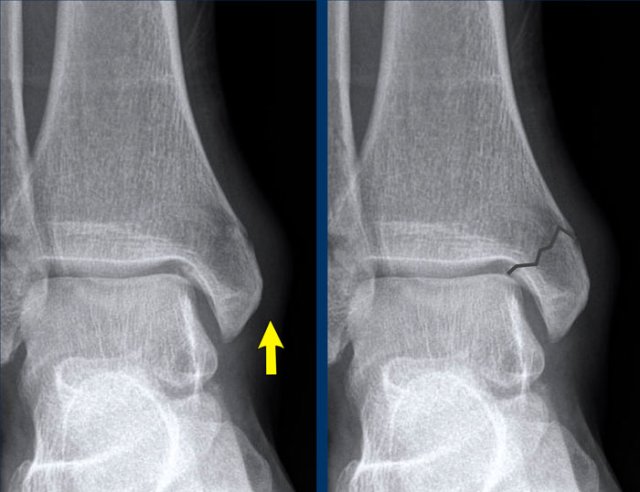

The findings are:

• vertical fracture of the medial malleolus (yellow arrow).

This is not an avulsion or pull-off fracture, but a push-off fracture.

• Maybe there is an avulsion of the lateral malleolus (white arrow), but that is not sure.

However this does not matter as we will show in a moment.

A vertical fracture of the medial malleolus is a push-off fracture.

According to Lauge-Hansen the fracture results from an adduction force on the supinated foot

The lateral side is under extreme tension with stretch on the lateral collateral band.

In stage 1 there is either a rupture of the lateral collateral band or an avulsion fracture (which we also know as Weber A).

In stage 2 there is always a vertical fracture of the medial malleolus and there has to be either an avulsion of the lateral malleolus or a rupture of the collateral band as these sequences always are in this order with first stage 1 and then stage 2.

This means, that whether we see a fracture on the lateral side or not, it doesn't matter.

There must be an injury to both the medial aswell as the lateral side and we now know that the ankle is unstable, because the ring of stability is broken in two places.

Here another unstable ankle fracture.

According to Lauge-Hansen this is SA stage 2.

According to Weber this is Weber A with additional fracture to the medial malleolus.